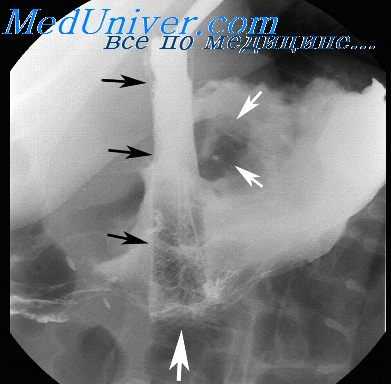

Опухоли пищевода. Рентгенологическая картина при опухолях пищевода зависит от характера процесса (доброкачественный или злокачественный), особенностей роста (экзофитный, эндофитный, смешанный), стадии развития (с изъязвлением или без него), локализации, а также нарушений функции, вызванных опухолью. Сама опухоль отображается на рентгенограмме в виде дефекта наполнения или сужения просвета пищевода, а вызываемые ее ростом изменения сказываются на картине рельефа слизистой оболочки (отклонение или разрушение складок), эластичности стенки и ее сократительной способности. При доброкачественных опухолях дефект наполнения имеет правильную форму (округлую, овальную или полуовальную) и в зависимости от проекции исследования может быть центральным, краевым и значительно реже — циркулярным. Контуры его, как правило, четкие, не всегда ровные. Во время акта глотания такой дефект легко смещается кверху вместе со стенкой пищевода. При преимущественно экзоэзофагеальном росте и значительных размерах опухоли на уровне дефекта наполнения на фоне заднего средостения может определяться дополнительная тень.

Именно отсутствием разрушения отклоненных или сглаженных складок слизистой оболочки в зоне расположения опухоли доброкачественные опухоли отличаются от полипоподобного рака. При доброкачественных опухолях практически почти полностью сохраняются эластичность стенки на уровне поражения и ее сократительная способность, а супрастенотическое расширение просвета над опухолью отсутствует. В связи с этим значительной задержки бариевой взвеси здесь не наблюдается и стенки пищевода растягиваются бариевым комком симметрично, а пораженный участок переходит в нормальную зону постепенно, без резких границ. Состояние эластичности стенок при доброкачественных опухолях пищевода особенно отчетливо определяется при рентгенокиносъемке [Кевеш Л. Е., 1965; Рабкин И. X. и др., 1969], а также при использовании видеомагнитной записи получаемого изображения.

При проведении рентгенографии пищевода с контрастированием выявляются дефекты наполнения, деформация просвета пищеводной трубки, изменения рельефа слизистой. По рентгенологической картине можно выделить опухоли, полностью находящиеся в просвете органа; растущие как в просвет, так и интрамурально; распространяющиеся из внутренних слоев пищевода кнаружи и сдавливающие его извне. Отличием доброкачественных неэпителиальных опухолей от рака является сохраненный рельеф слизистой и эластичность стенок пищевода на уровне расположения новообразования. Диагноз подтверждается гистологически.

Диагностика и лечение злокачественных опухолей пищевода

Диагностирование злокачественных опухолей пищевода обычно включает в себя эзофагоскопию с биопсией, контрастную рентгенографию пищевода, МРТ и компьютерную томографию. Признаки, которые говорят в пользу злокачественного новообразования: нетипичное изменение рельефности слизистой; неравномерность контуров пищеводной стенки или дефект наполнения, сопровождающийся отсутствием перистальтики на этом уровне; неравномерность просвета пищевода, стеноз пищевода с расширением просвета над опухолевым узлом, подрытые контуры стенки пищевода на границе здоровой ткани и опухоли. Компьютерная томография позволяет с большой вероятностью определить возможности оперативного лечения, составить прогноз для выздоровления и жизни пациента.